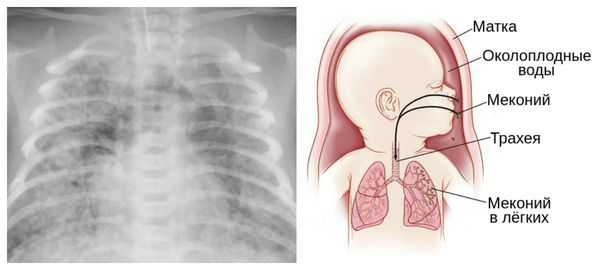

Пролонгацией физиологической беременности считают увеличение сроков гестации до 290-294 дней при отсутствии признаков старения плаценты и перезрелости плода. При истинном перенашивании беременность заканчивается рождением перезрелого плода с морфофункциональными изменениями в плаценте. К признакам переношенной беременности относится уменьшение количества околоплодных вод, отсутствие первородной смазки, сморщивание и сухость кожи ребенка, появление в водах примеси мекония, вследствие чего их цвет становится сероватым или зеленоватым.

Картина УЗ-исследования при переношенной беременности характеризуется уменьшением общего объема и полным отсутствием «передних вод», отсутствием хлопьевидных включений сыровидной смазки в амниотических водах, наличием в водах мекония. Допплерография маточно-плацентарного кровотока определяет признаки старения плаценты, которая в полной мере не обеспечивает питание и кислородное снабжение плода: петрификаты в плаценте, уменьшение ее толщины, сниженную интенсивность фетоплацентарного и маточно-плацентарного кровотока. Все эти данные указывают на перезрелость плода и испытываемую им гипоксию. Уменьшение ЧСС плода (менее 110-120 уд. в мин.) или увеличение (свыше 160 уд. в мин.) по результатам кардиотокографии подтверждают нарушения в состоянии плода.

Для диагностики переношенной беременности может применяться методика цервикальной амниоскопии - эндоскопического исследования характера околоплодных вод через неповрежденную стенку плодного пузыря. Зеленоватый цвет вод, свидетельствующий о примеси мекония, указывает на внутриутробную гипоксию плода. Амниоскопия может проводиться только в ситуациях, когда шейка матки мягкая и приоткрыта для введения прибора.

Опасности переношенной беременности для ребенка заключаются в возможной гипоксии плода и асфиксии новорожденного, развитии поражений головного мозга, получении родовых травм, аспирации мекония и околоплодных вод. Состояние детей, родившихся от переношенной беременности, отягощается выраженной желтухой, гормональными кризами, инфекционными поражениями кожи, неврологическими нарушениями. Впоследствии они нередко отстают от нормального физического и психического развития.

Из-за снижения кровотока в почках плода выделение мочи значительно уменьшается, развивается маловодие. Также изменяется характер околоплодных вод: они теряют прозрачность, становятся мутными, приобретают желтоватый или зеленоватый оттенок из-за примеси мекония — первых фекалий ребёнка.

Для плода большую опасность представляет асфиксия (острая гипоксия) и отслойка плаценты. Нехватка кислорода внутри утробы стимулирует плод выполнить несвоевременные дыхательных движения. Они приводят к заглатыванию вод и возможному воспалению лёгочной ткани — пневмониту. Если в водах есть примесь мекония (первородного кала), то велика вероятность мекониальной аспирации — проникновения содержимого кишечника новорождённого в его лёгкие.